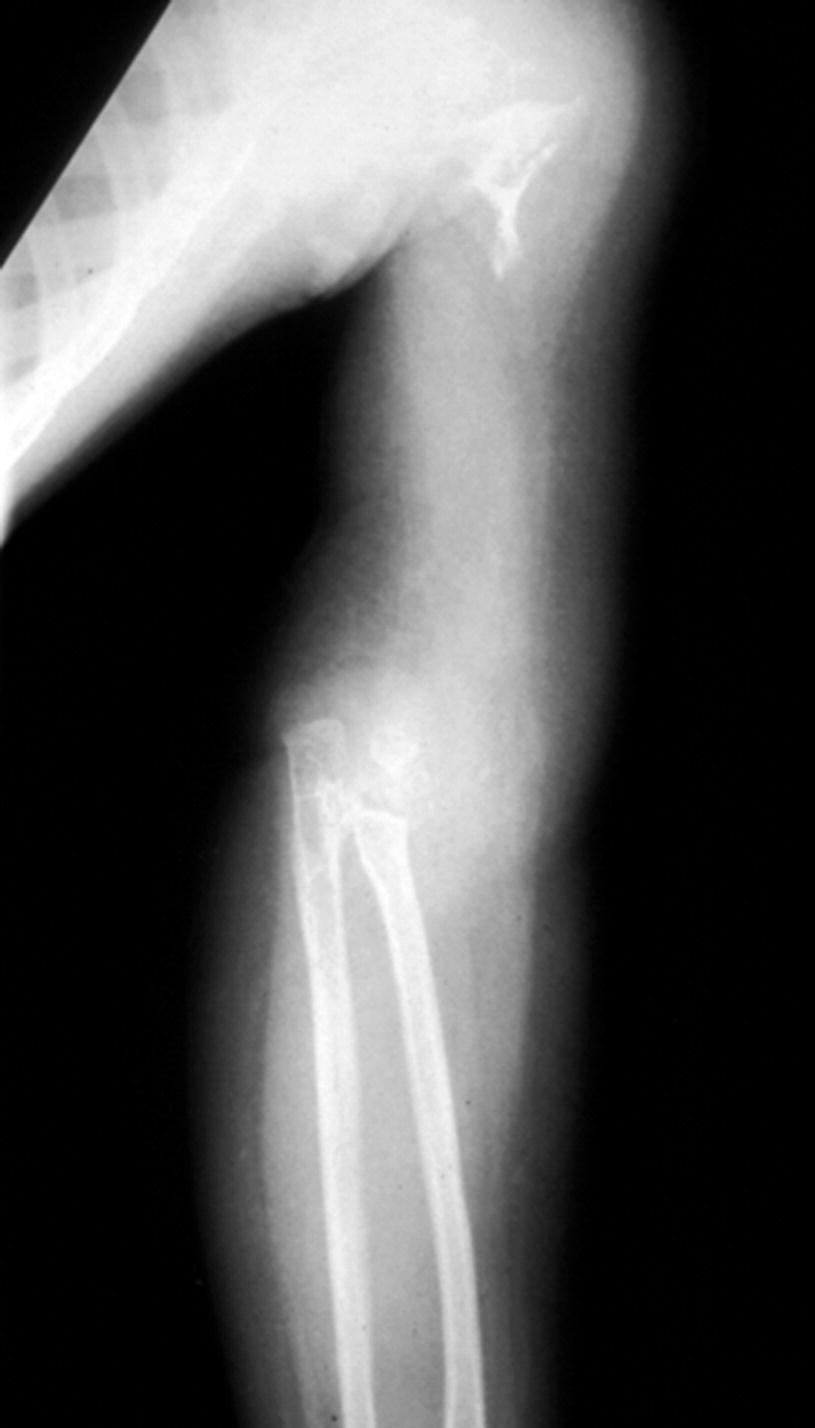

A Rare Case Of Progressive Gorham S Disease Of Right Shoulder Girdle And Cervical Spine In A Child 10 Year Follow Up And A Review Of Literature Journal Of Orthopaedic Case Reports